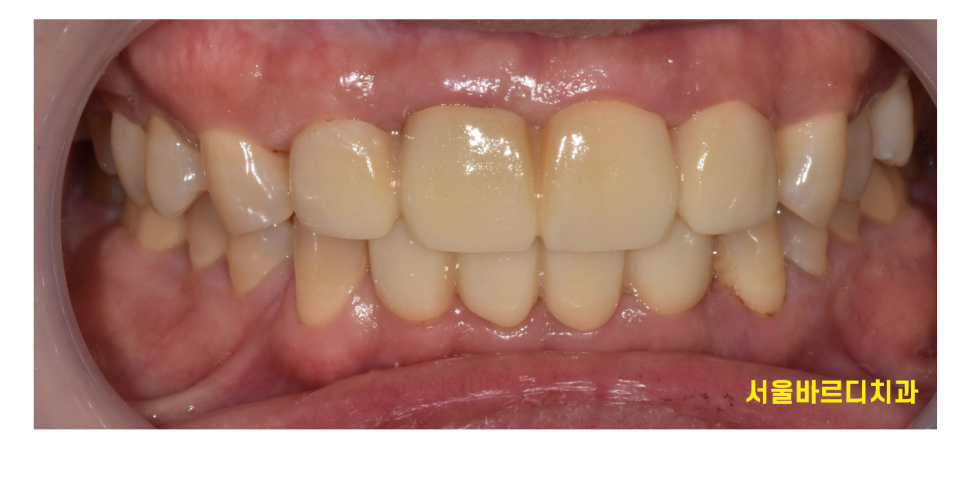

오늘의 환자분은 50대 중년 남성분입니다.

앞니 사이 간격 넓어짐이 점점 심해진다고 내원 주셨는데요

윗니, 아랫니 두개 모두 사이가 많이 벌어졌네요~

오늘 환자분은 위아래 앞니 모두 사이 사이 공간이 있었습니다.

벌어진 공간이 꽤 컸기 때문에

레진이나 라미네이트로는 한계가 있었습니다.

치아 사이즈가 더 커져서

비슷한 크기로 조화롭게 치료하기 위해서는

앞니를 크라운 치료를 통해 벌어진 것을 메꾸기로 했습니다.

예쁘게 치료가 되었습니다.

치료가 끝난 후 환하게 웃으시던 환자분

"원장님 이제 음식물도 안끼겠어요~"

좋아하시던 모습이 기억납니다.